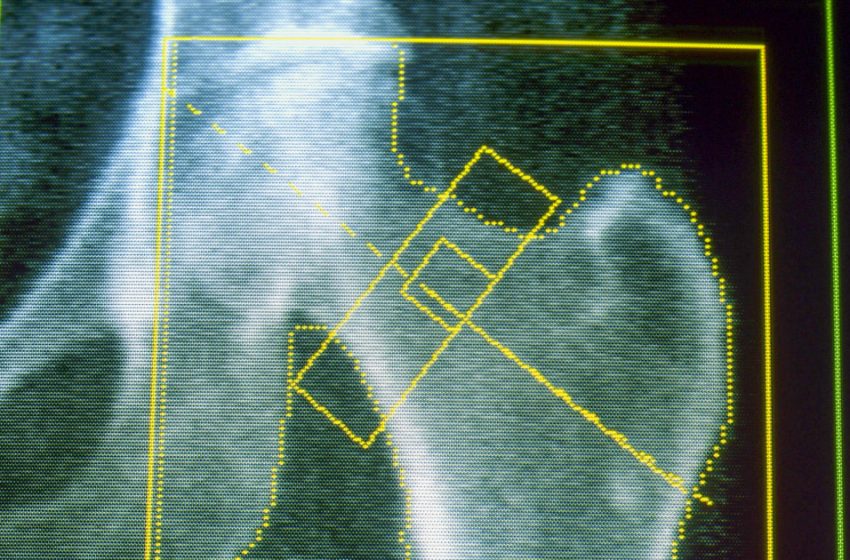

Osteoporosis is a disease that weakens the bones and makes them likelier to break or fracture, often from minor falls. It’s a common concern for many older adults and for people who lose a significant amount of weight over a short period of time. Gout, meanwhile, is a painful form of arthritis that can occur when the body has too much uric acid, which can come from a diet high in red meat and alcohol — as well as rapid weight loss.

About 4% of GLP-1 users developed osteoporosis, compared with a little over 3% of nonusers — an increased risk of about 30%. A related condition, osteomalacia, which involves the softening of the bones, was rare but also occurred about twice as often among people on GLP-1s.